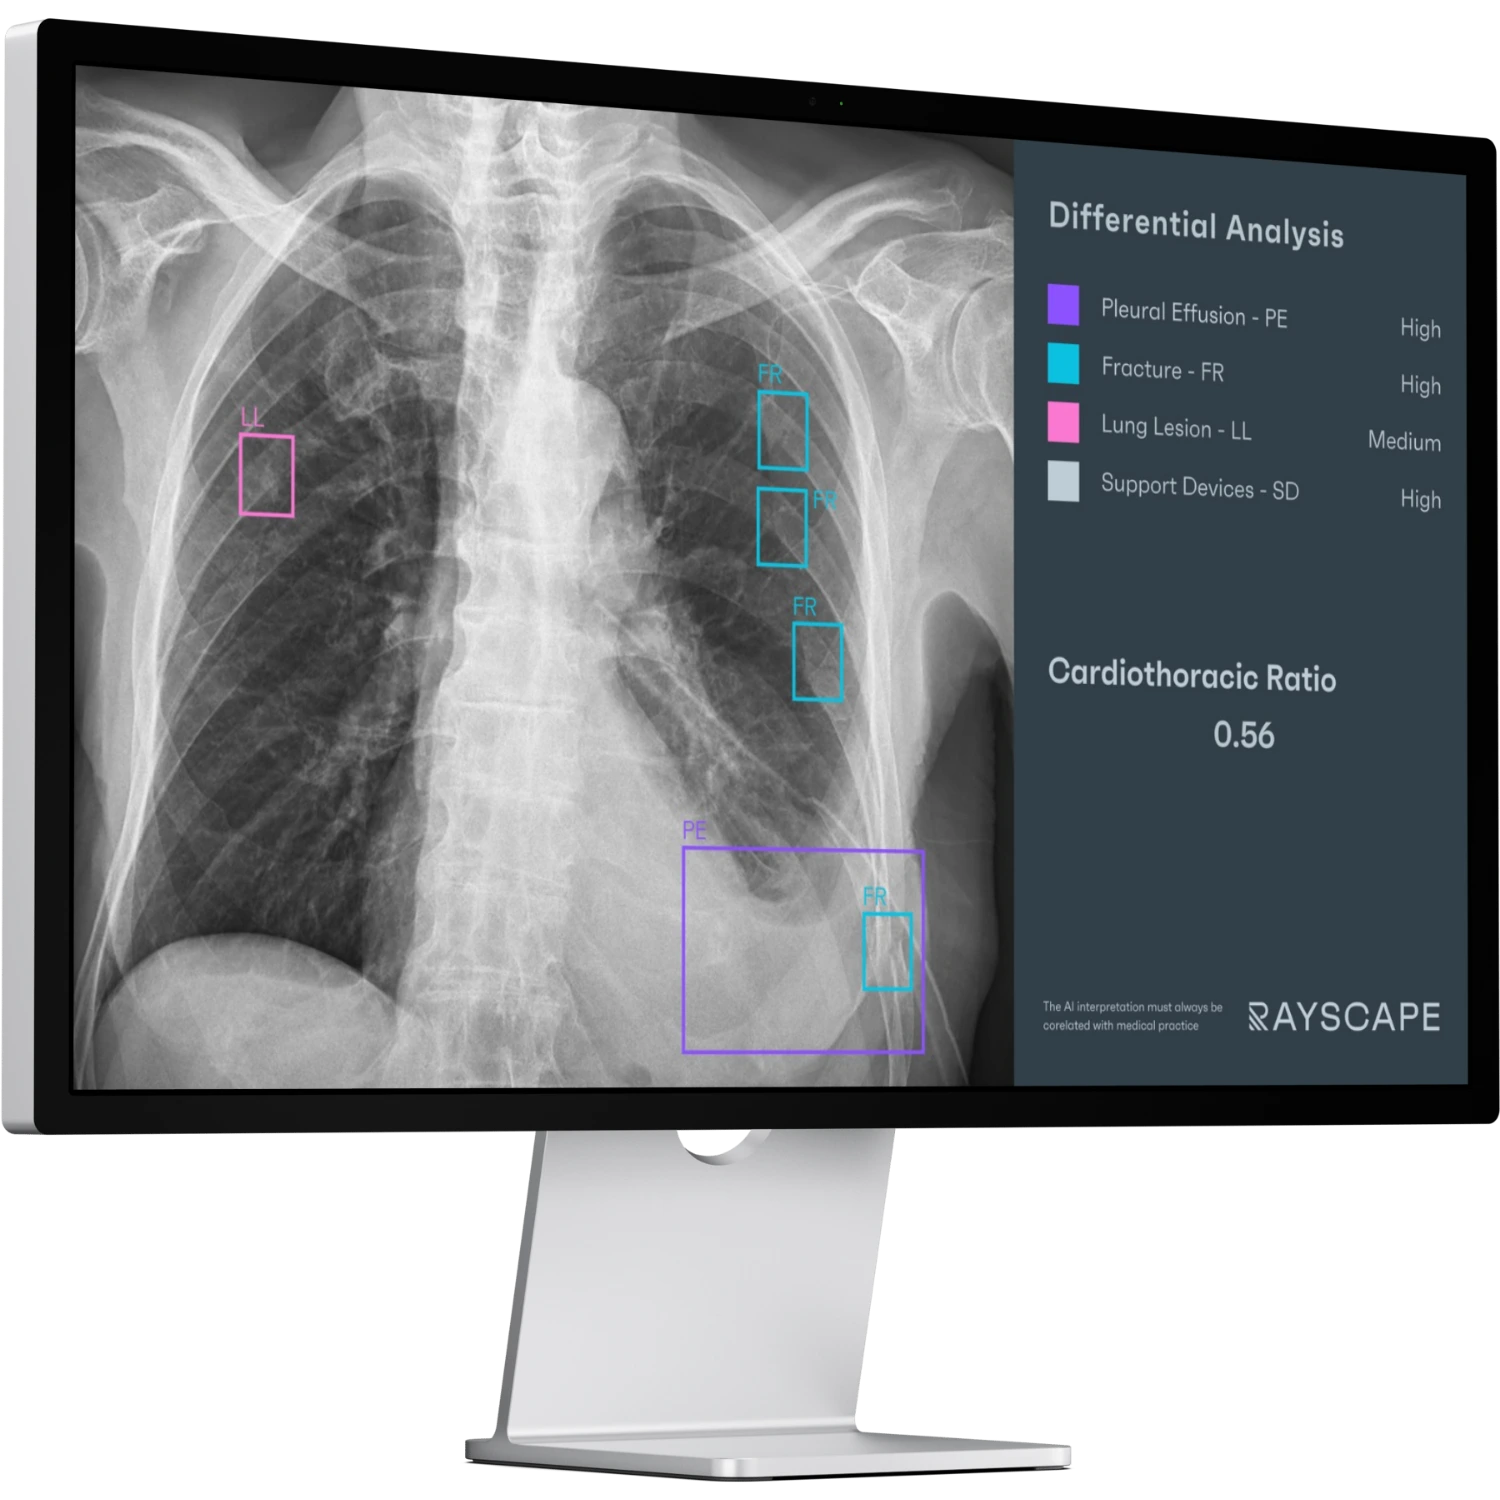

AI DETECTION

CASE PRIORITIZATIONRAYSCAPE CXR AI brings computational clarity to everyday imaging, continuously analyzing chest X-rays to surface clinically meaningful patterns that might otherwise remain buried in visual complexity. By combining broad abnormality detection with advanced image enhancement, the system helps transform raw imaging data into structured, actionable insight.

Designed to function as a second reader rather than a separate system, Rayscape enhances rapid case review, recognition of acute changes, and structured communication without altering established reading workflows. The solution is DICOM-compliant, compatible with standard hospital IT environments, and built to scale from individual small radiology departments to large hospitals, delivering advanced AI support with minimal operational friction.